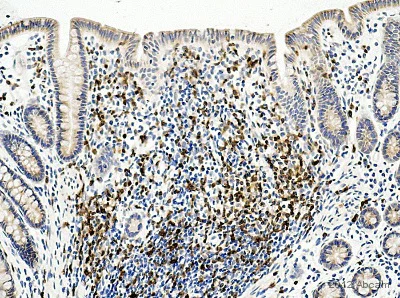

Immunohistochemistry (Formalin/PFA-fixed paraffin-embedded sections) - Anti-CD3 antibody (AB828)

• IHC-P

AbReview31995****

IHC-P image of CD3 staining on monkey colon using ab828 (1 : 50). The section was deparafinized, rehydrated and subjected to heat mediated antigen retrival using citric acid at pH6. The section was then blocked using 1% BSA at 21°C for 10 mins. The primary antibody was used at 21°C for 2 hours. Goat polyclonal to Rabbit IgG conjugated to biotin was used as secondary antibody (1 : 250).

This image is courtesy of an abreview submitted by Carl Hobbs, King's College London, United Kingdom